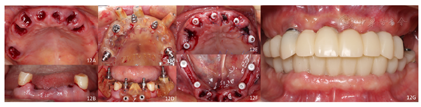

架;④排牙,制作放射导板(图6A);⑤试戴放射导板(图6B~D),拍摄两次CBCT(患者佩戴放射导板拍摄CBCT以及放射导板单独拍摄CBCT)。(2)方案设计:①将两次CBCT获取的DICOM数据导入种植设计软件重叠(图7),以修复为导向指导上下颌种植体位置摆放(图8、图9);②生成并打印手术导板(图10)。(3)利用手术导板和导板锁,翻制模型,制作临时修复体(图11)。(4)一期手术过程:铺巾消毒,局麻后拔除上下颌余留牙,搔刮拔牙窝内炎性肉芽组织,于34-36、44-46区牙槽嵴顶近远中向切开牙龈,翻瓣。就位并固定手术导板,于11、13、16、22、25、26、32、34、36、42、44、46定点,按术前设计方案植入NobelParallelTM ConicalConnection种植体。除26区种植体外,其余种植体初期稳定性均达到35N.cm以上,就位复合基台,戴入保护帽,修整牙龈黏膜,缝合牙龈(图12A~F)。术后拍摄全景片(图13)。次日复诊,取下保护帽,戴入预制的临时修复体,调合(图12G)。

治疗结果:术后3个月全景片显示种植体骨结合良好(图14)。26牙行二期手术,就位复合基台,戴入保护帽。两周后,取下临时修复体,制取上下颌硅橡胶印模,利用临时修复体交叉上

面。戴入最终修复体,调合(图17)。种植修复前后面像对比,患者面下1/3高度恢复良好(图18)。

术后一年随访:拍摄全景片显示种植体周围骨结合良好,边缘骨高度稳定(图19)。义齿外形无变化,下颌义齿前牙区舌侧面见牙结石。